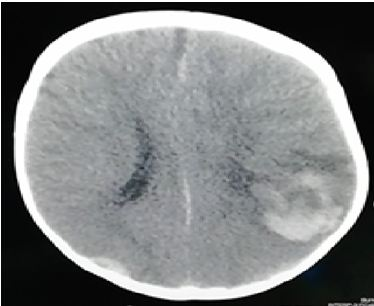

On examination, He looked well but pale. His weight was 11kg (normal), the length was 76cm (normal) and his head circumference was 47cm (normal). Cardiovascular, respiratory, and abdominal examinations were normal. The blood pressure (BP) was 100/60mmHg, oxygen Saturation (Sao2): 98%, the pulse rate was 110/min, body temperature was 37⁰C and respiration rate was 40/min. His spine and joints appeared normal, and there were no unusual birthmarks. Neurological examination showed normal cranial nerves and normal posture, tone, power, and reflexes in the upper and lower limbs. There were no focal neurological signs and no other signs. Funduscopic examination showed Roth's spots spread with cloudy papilla borders and ulceration vessels with flame bleeding. Contrast-enhanced computed tomography (CT) of the brain showed right intra-cerebral bleed extending from the parietal lobe to the occipital region with a shift of the midline (Figure 1). Laboratory results were as in Table 1.

Figure 1 CT scan of brain showed parenchymal, epidural and subdural hemorrhage in the right parietal and occipital region with deviation of median.